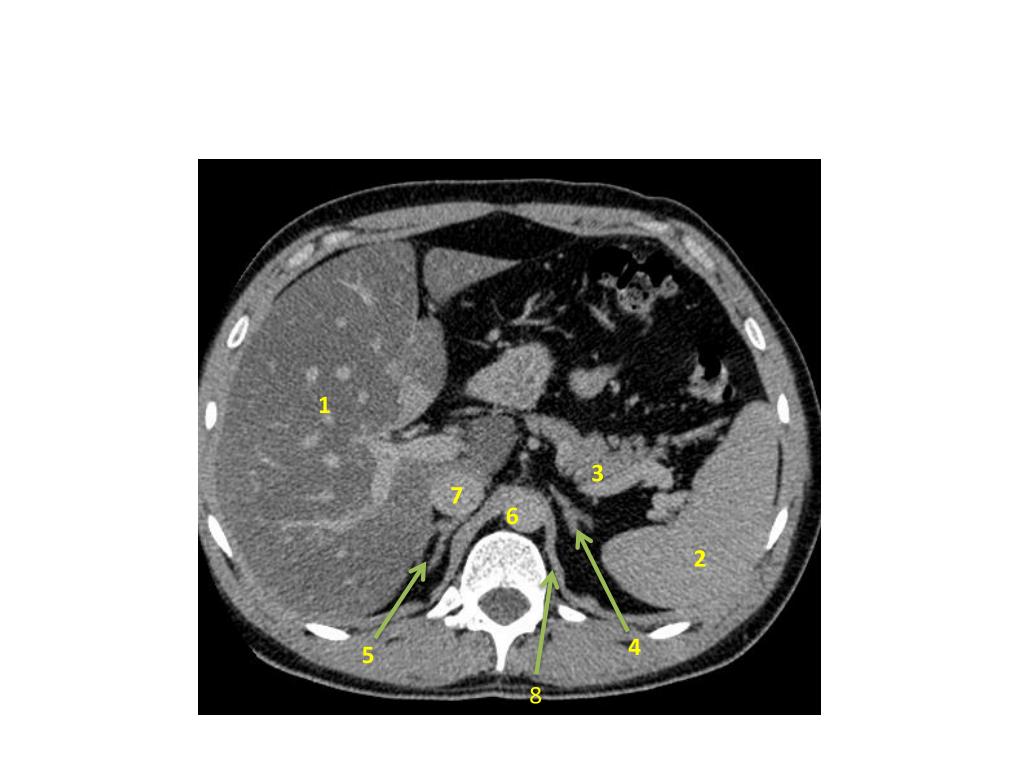

3. 1- Liver 2-Spleen 3- Pancreas 4- Left adrenal gland 5- Right adrenal gland 6- Aorta 7- IVC 8- left crus of the diaphragm. 1 3 7 6 2 5 4 8